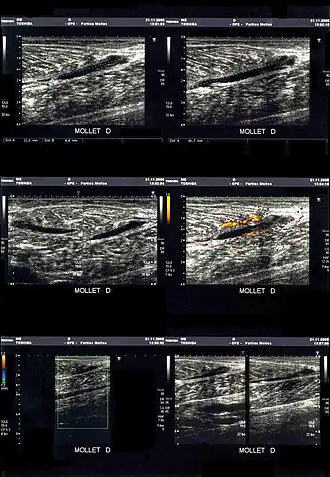

La déchirure apparait sous la forme d'une zone hypoéchogène (sans écho, et donc noire).

En cas de doute ou pour préciser les dégâts musculaires dans les cas les plus graves, une déchirure peut être mise en évidence par l'imagerie médicale[15] :

- échographie/échotomographie : « examen le plus utile et le moins cher, permet une étude des fibres musculaires, des tendons et des aponévroses. Ses limitations sont la mauvaise analyse des zones profondes, comme l’insertion proximale des ischio-jambiers, et la difficulté à détecter parfois les cicatrices »[3].